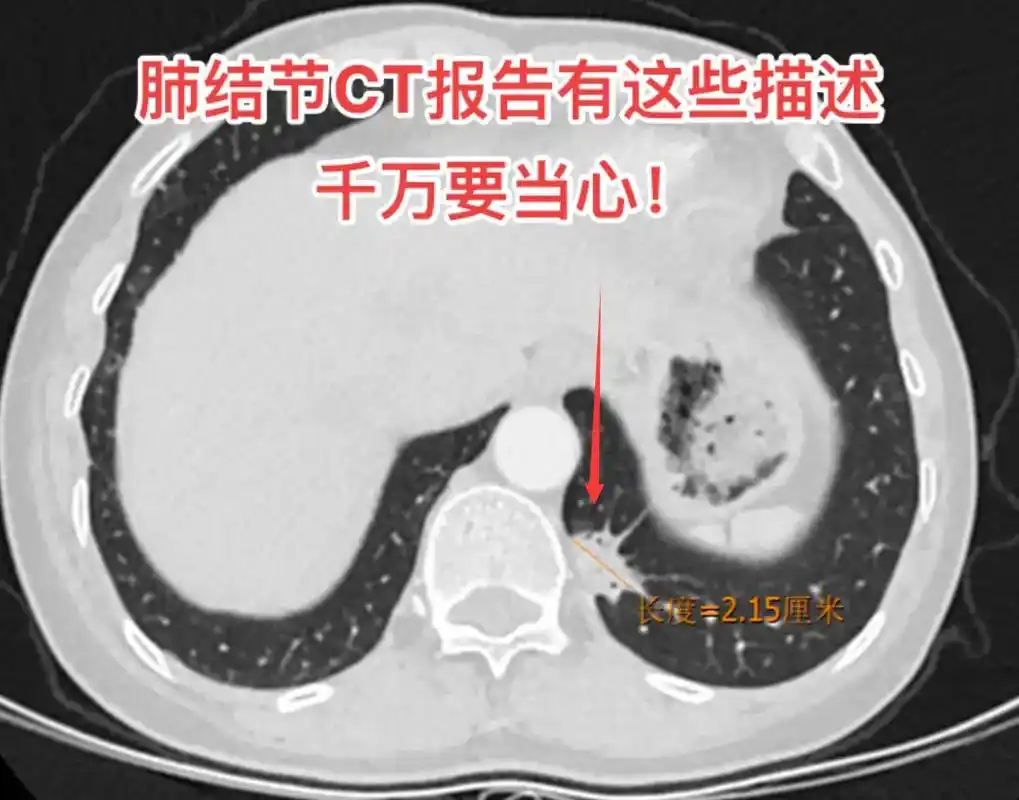

肺结节ct报告有这些描述千万要当心!1.分叶和毛刺;2.空泡 - 抖音

肺结节到底是良性,还是恶性,如何辨别?这些特征需警惕

图文教你看懂恶性肺结节的ct表现

实性肺结节的良恶性ct征象解析